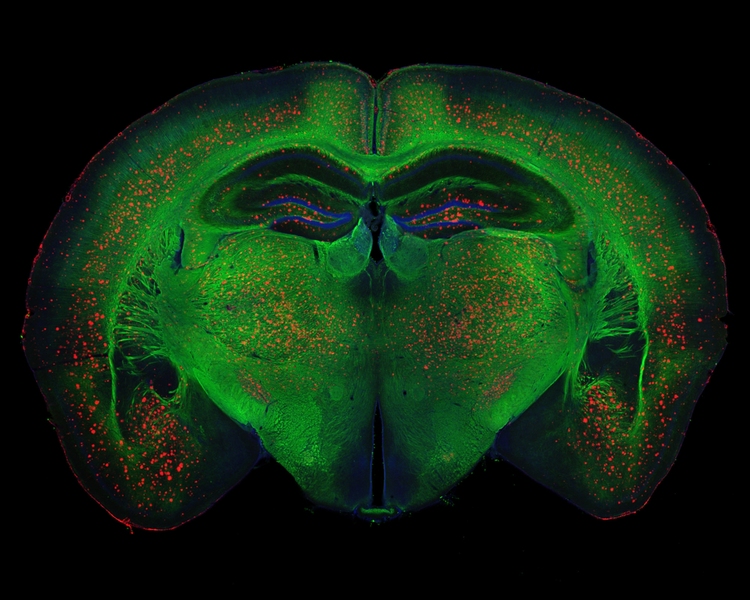

Beta-amyloid plaque deposits (red) disrupt mylelin (green) organization in the brain and activate microglia (orange), driving the inflammation, neurodegeneration, and cognitive disfunction associated with Alzheimer's disease.

Image: Rebecca Canter